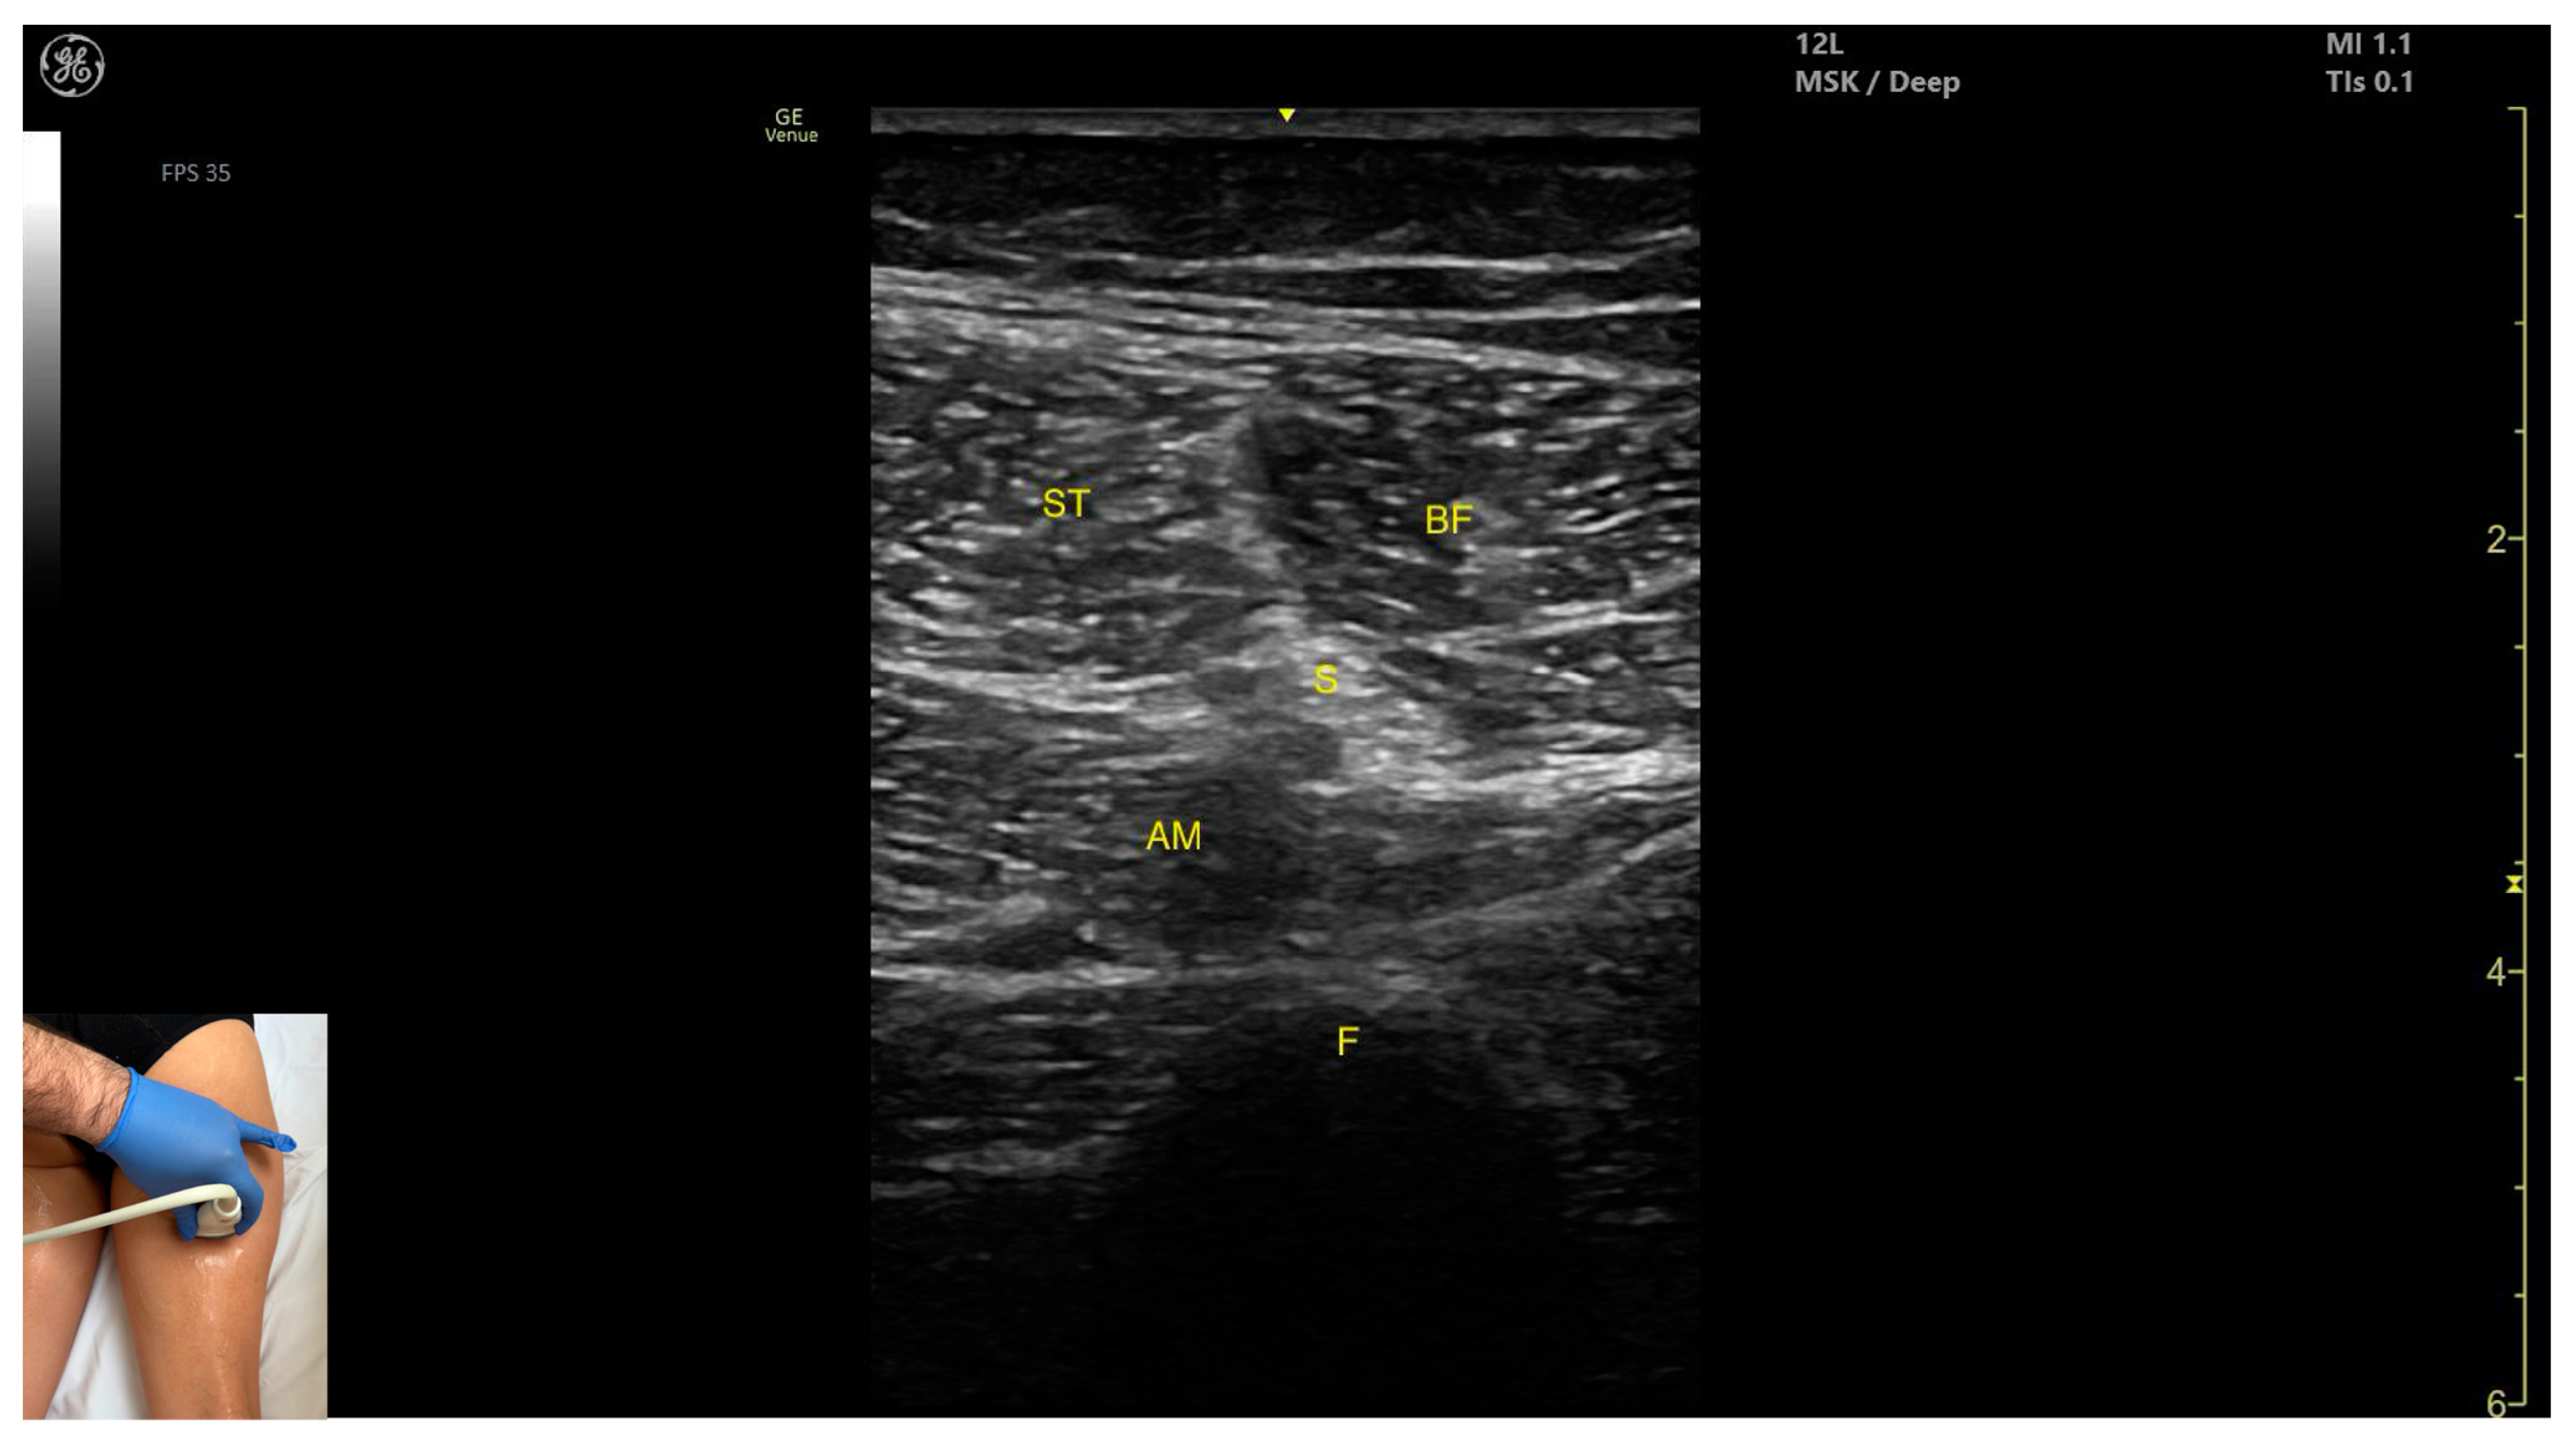

3.10. Semitendinosus (ST)

3.10.3. Key Ultrasound Landmarks

- Muscle position: It appears as a superficial muscle mass at this level. It is the second muscle from medial to lateral in the proximal third of the posterior thigh. It is bordered medially by the semimembranosus and laterally by the biceps femoris. The sciatic nerve lies deep and lateral to the ST and deep to the biceps femoris.

- Muscle morphology: The “Mercedes-Benz sign” may be seen—an ultrasound pattern created by the intersection of the fascial planes of the ST, biceps femoris, and adductor magnus, with the sciatic nerve centered between them. A characteristic “Venetian blind” appearance can be observed—this refers to the vertical intramuscular fascia traversing the muscle’s width. It appears as alternating hyperechoic and hypoechoic bands resembling the slats of a Venetian blind, resulting from the regular alignment of muscle fibers and connective septa reflecting ultrasound waves (Video S3).

- External fascia: It features a pronounced fascia that separates it from the subcutaneous layer, adductor magnus, semimembranosus, and biceps femoris, which is crucial for safe BoNT-A injection.

- Dynamic evaluation: During dynamic scanning distally toward the knee joint, the ST decreases in thickness, while the semimembranosus increases. The sciatic nerve maintains its course deep and lateral to the semitendinosus. Muscle contraction is visible during hip extension, knee flexion, and the internal rotation of the leg.

3.10.4. Clinical Implications and Injection Strategy

3.11. Biceps Femoris (BF)

3.11.3. Key Ultrasound Landmarks

- Muscle morphology: It has two heads: the long head (medial) and the short head (lateral), which can be approached individually, separated by an intramuscular fascia.

- Muscle position: It appears as a superficial muscle mass and is the most lateral muscle in the posterior (flexor) compartment of the thigh at this level. The long head lies adjacent to the sciatic nerve, which runs underneath the muscle.

| S | Sciatic (nerve) |

| ST | Semitendinosus (muscle) |

| Semitendinosus | Proximal third of posterior medial thigh | Semimembranosus (medial), biceps femoris (lateral), adductor magnus (deep), and sciatic nerve (deep and lateral) | Transverse scan on posterior thigh | Visualize characteristic ’Mercedes-Benz’ and ’Venetian blind’ signs, avoid nerve injury |